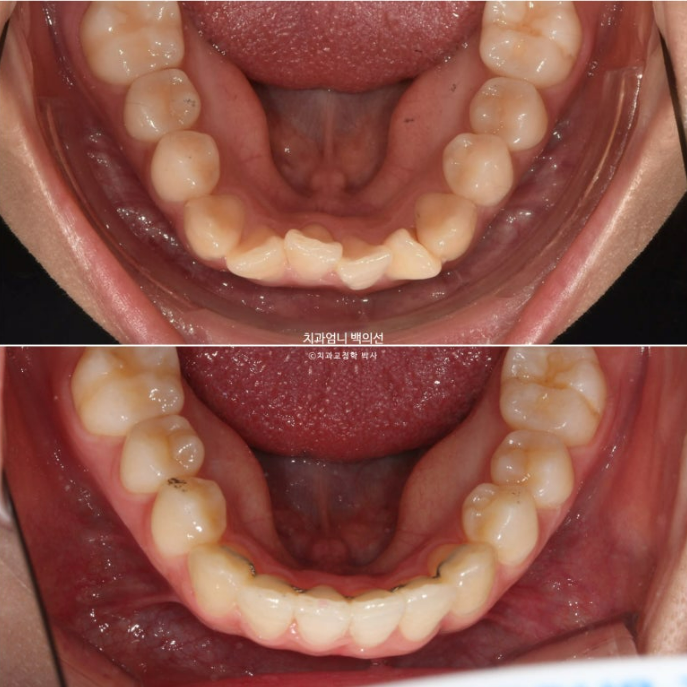

아래 앞니가 많이 삐뚭니다.

부분교정에서는 앞니 배열될 공간을 소량의 치간삭제로 얻습니다.

앞니 부분교정용 장치 중 MTA 장치를 선택하셨고 치료에 들어갔습니다.

MTA 장치는 송곳니부터 송곳니까지 앞니에만 붙여서 배열을 진행했고 나머지 작은어금니와 큰어금니는 움직이지 않았습니다

아무래도 파란 화살표 작은어금니 덧니가 옥의티죠?

아쉽지만, 환자분이 투자한 비용과 시간, 노력 대비 앞니 부분교정 급속교정 만으로도 좋은 효과를 봤으니 눈을 질끈 감겠습니다.

24.09

유지장치까지 붙은 모습입니다. 총 치료기간은 9개월입니다.

이제 전 후 비교사진 보겠습니다.

23.12~24.09

고무줄 사용으로 송곳니 교합관계도 개선이 되었습니다.

가지런한 앞니 배열과 철사 유지장치